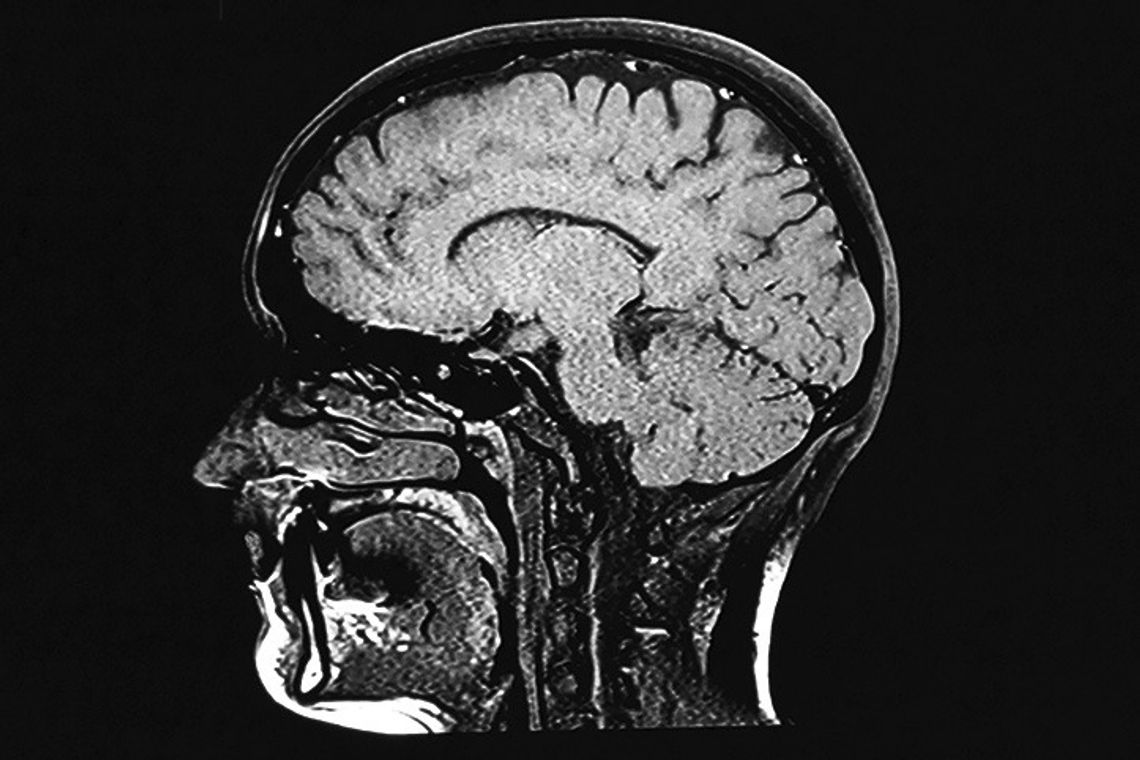

Mild traumatic brain injuries are more common than people may realize. While the prevalence of concussions among competitive athletes is widely recognized, one need not play a sport to suffer a mild traumatic brain injury.

The Centers for Disease Control and Prevention reports that anyone can experience a traumatic brain injury (TBI). A 2019 study published in the journal JAMA Insights noted that mild traumatic brain injuries (mTBIs) are the most common type of TBI. Despite their characterization as “mild,” mTBIs can produce physi c a l , cognitive and social or emotional symptoms. Recognition of the signs of mTBIs may compel people experiencing such injuries to seek medical attention that can make life more manageable until symptoms subside.